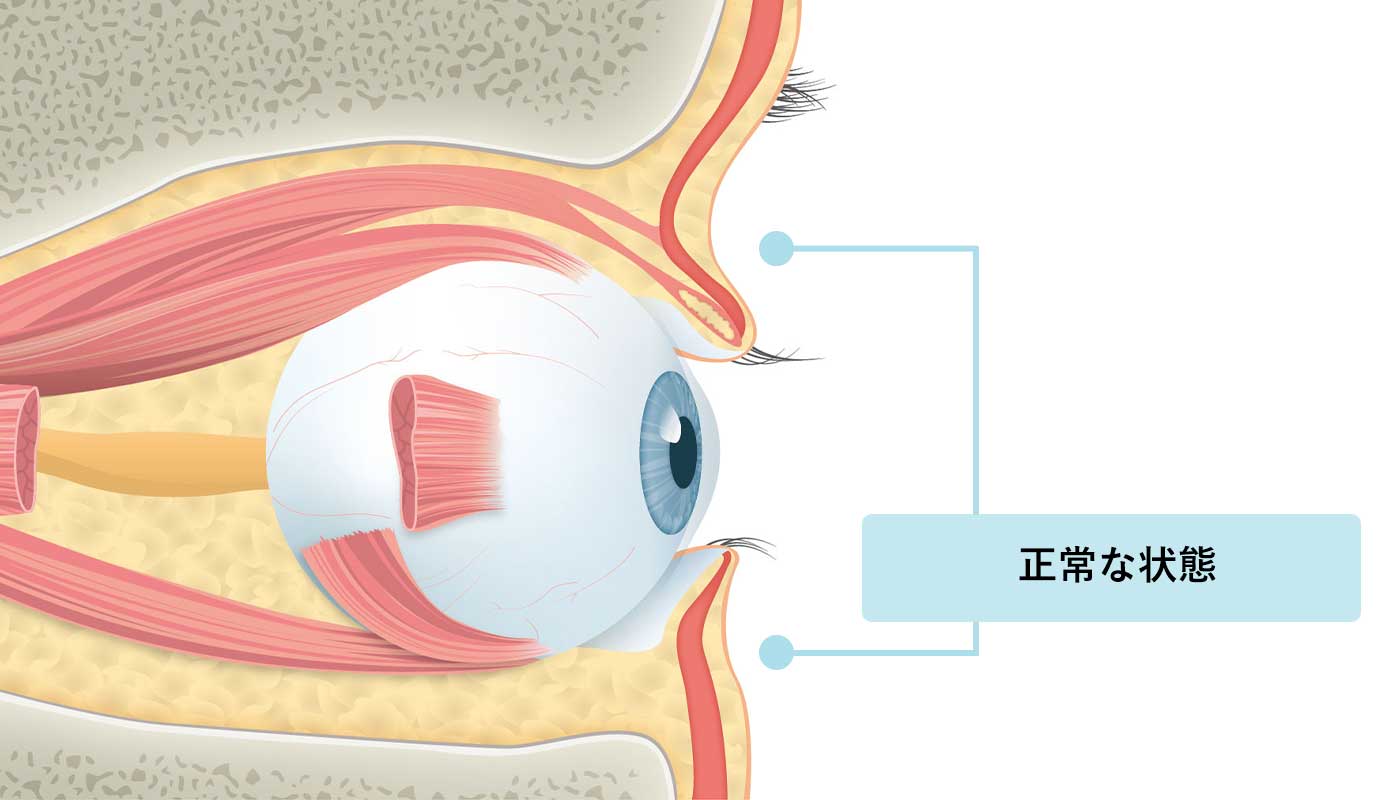

正常な状態

上のまぶたの凹みもなく、正常な状態です。